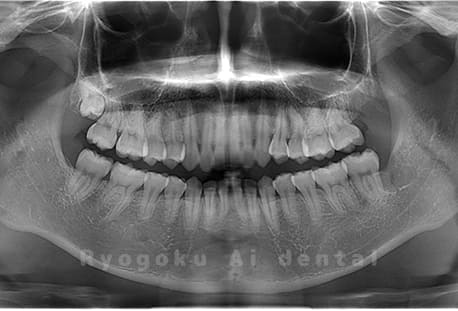

Case01

- 原因

- 水平埋伏智歯

- 治療内容

- 下顎の水平埋伏智歯を抜歯

<リスク・副作用>

手術後は痛み、腫れ、痺れなどの副作用が生じる場合があります。